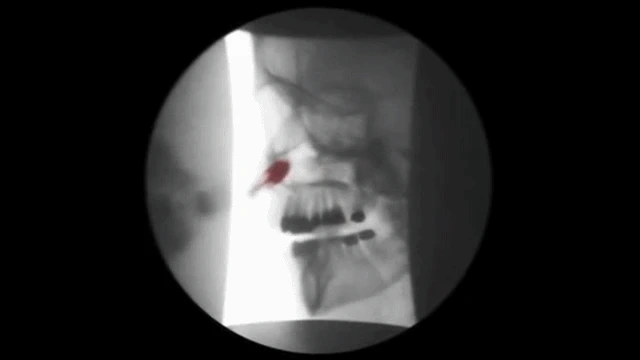

저는 CFRT 의 교정 시술법을 사용하고

있는데요, CFRT 는 그 역사가 80여년

이상된 두개안면 교정술로 조그만 풍선을

콧구멍으로 넣어서 비강과 인두사이에

위치한 두개안면의 구조물을 확장시키는

원리의 시술법입니다. 아래의 그림처럼

들어간 풍선이 연구개나 목젖을 통과하게

되면서 늘어진 연부조직을 수축시키고

좁아진 호흡통로를 넓혀주는 방법 입니다.